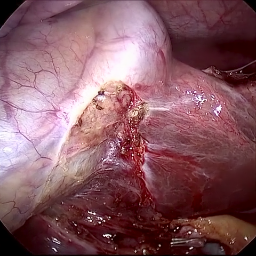

Refer to caption (a) Input Refer to caption (b) DIACMPN Refer to caption (c) Desmoke-LAP Refer to caption (d) PFAN Refer to caption (e) MITNET Refer to caption (f) Salazar Refer to caption (g) Dehamer Refer to caption (h) Ours Refer to caption (i) Target

Figure 2: Comparison of different methods on the DesmokeData dataset.

Figure 3: Comparison of different methods on the LSD3K dataset.

IV-C2 Qualitative Analysis

Figures 3 and 2 provide a visual comparison of the desmoking results on challenging images from the test sets. The visual results corroborate our quantitative findings. DCP not only fails to remove the dense smoke but also introduces severe color distortion. CNN-based methods like FFA-Net and MSBDN successfully remove a large portion of the smoke but tend to either leave behind a thin layer of residual haze or over-smooth the image, losing critical textural details of the tissue and surgical instruments. The Transformer-based methods, DehazeFormer and PFAN, produce significantly better results by restoring more details. However, they can sometimes struggle with non-uniform smoke distribution, resulting in regions with unnatural brightness or minor artifacts.

In stark contrast, our RGA-Net generates visually superior results that are remarkably close to the ground-truth images. It effectively removes even the densest plumes of smoke while simultaneously preserving fine-grained details, such as blood vessels, tissue textures, and reflections on surgical tools. Furthermore, the color and illumination of the restored scene appear more natural and consistent, which is a direct benefit of our model’s ability to handle both local and global features through its hybrid attention and cross-gating mechanisms. This enhanced visual clarity is crucial for improving the surgeon-robot interface in real-world clinical applications.